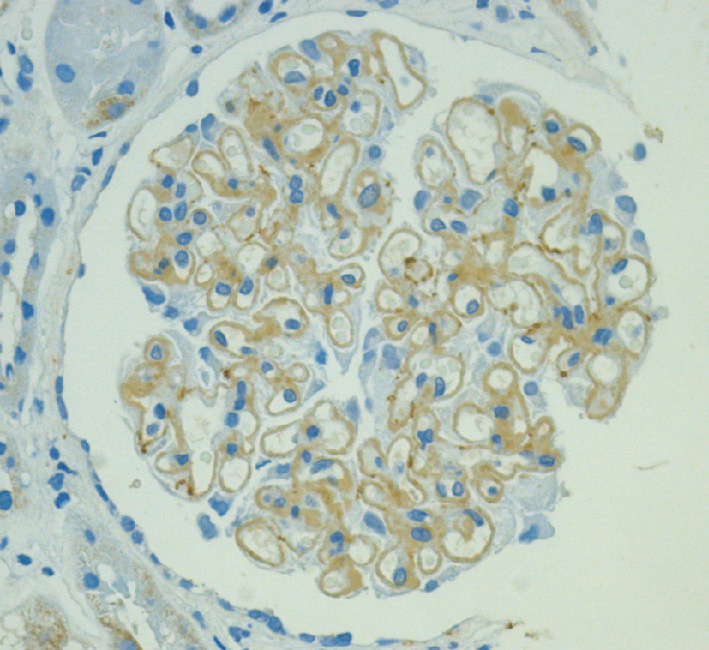

肝臓病学 朝倉書店 小児栄養消化器肝臓病学 | 日本小児栄養消化器肝臓学会 |本の詳細情報

小児栄養消化器肝臓病学 | 日本小児栄養消化器肝臓学会 |本。肝臓病学 朝倉書店 医学一般。朝倉内科学 第12版。朝倉書店『内科学』(第12版)デジタル付録。「肝臓病学」井廻 道夫 / 熊田 博光 / 坪内 博仁定価: ¥ 20000+税購入後、使うことなく埃や光が当たらない所で保管していました#井廻道夫 #井廻_道夫 #熊田博光 #熊田_博光 #坪内博仁 #坪内_博仁 #本 #自然/医療・薬学・健康